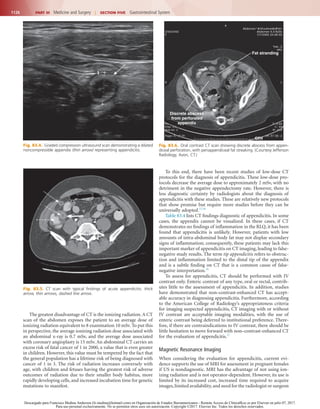

Fig. 83.5.  CT scan with typical findings of acute appendicitis. thick

arrow, thin arrows, dashed line arrow.

Fig. 83.6.  Oral contrast CT scan showing discrete abscess from appen-

diceal perforation, with periappendiceal fat streaking. (Courtesy Jefferson

Radiology, Avon, CT.)

Fat stranding

Discrete abscess

from perforated

appendix